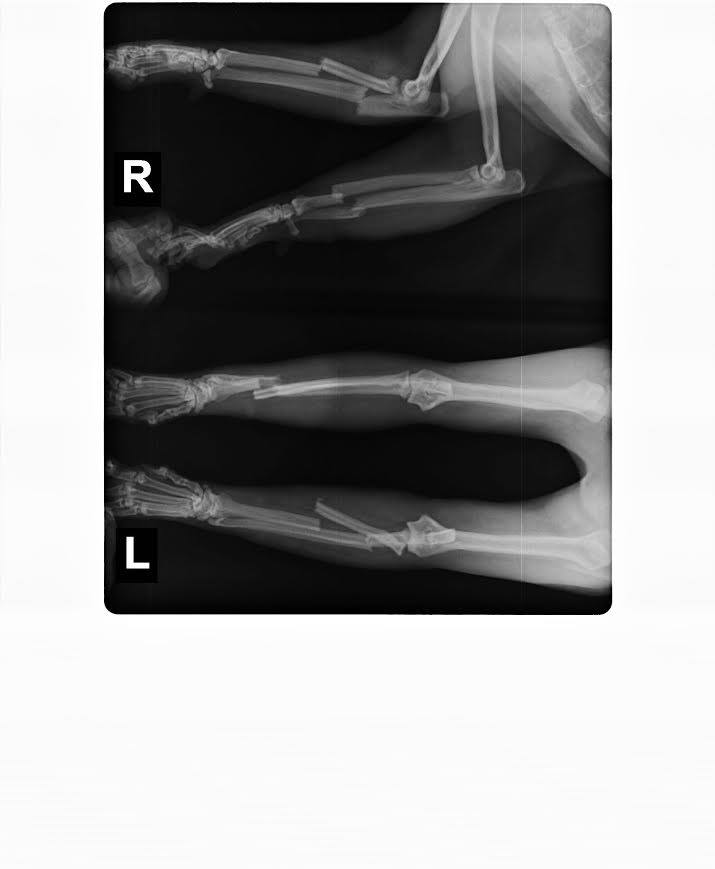

"Jaunmārupē atrasts smagi traumēts kaķītis, kurš, visticamāk, cietis no kāda transporta līdzekļa. Minkam ir 4 kaulu lūzumi abās priekšķepiņās, arī lauzts apakšžoklis un ceturtdien, 9. jūnijā, notiks operācija, kura maksā 200 eiro. Mīļie līdzcilvēki, ļoti lūdzam ziedot viņa operācijai, kā arī atlabšanas periodam veterinārajā klīnikā, kurš ilgs vismaz mēnesi un izmaksās vēl aptuveni 200 eiro. Tātad kopā, lai mincis būtu atkal uz ķepām, nepieciešami vismaz 400 eiro!" vēsta ieraksts dzīvnieku patversmes Facebook lapā.